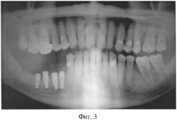

На Фиг.3 - ортопантомограмма пациента через 2 мес после имплантации.Figure 3 - orthopantomogram of the patient 2 months after implantation.

Через 3 месяца на первом этапе лечения было установлено 4 винтовых внутрикостных имплантата. Фиг.3 - ортопантомограмма больного после установки зубных внутрикостных имплантатов.After 3 months, at the first stage of treatment, 4 screw intraosseous implants were installed. Figure 3 - orthopantomogram of the patient after the installation of dental intraosseous implants.

Послеоперационный период протекал без осложнений. Рана зажила первичным натяжением.The postoperative period was uneventful. The wound healed by primary intention.